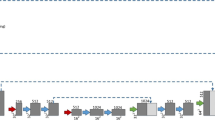

We selected patients whose interval between MRI and FDG PET/CT scans was within 3 months, from January 2017 to December 2018, and classified them into mild, moderate, and severe groups by following the semiquantitative rating method of Fazekas. For each group, 50 patients were selected, and of them, we randomly selected 35 patients for training and 15 for testing. WMH were automatically segmented from FLAIR MRI with manual adjustment. Patches of WMH were extracted from 18F-FDG PET and segmented MRI. WhyperGAN was compared with H-DenseUnet, a deep learning method widely used for segmentation tasks, for segmentation performance based on the dice similarity coefficient (DSC), recall, and average volume differences (AVD). For volume estimation, the predicted WMH volumes from PET were compared with ground truth volumes.

The DSC values were associated with WMH volumes on MRI. For volumes >60 mL, the DSC values were 0.751 for WhyperGAN and 0.564 for H-DenseUnet. For volumes ≤60 mL, the DSC values rapidly decreased as the volume decreased (0.362 for WhyperGAN vs. 0.237 for H-DenseUnet). For recall, WhyperGAN achieved the highest value in the severe group (0.579 for WhyperGAN vs. 0.509 for H-DenseUnet). For AVD, WhyperGAN achieved the lowest score in the severe group (0.494 for WhyperGAN vs. 0.941 for H-DenseUnet). For the WMH volume estimation, WhyperGAN performed better than H-DenseUnet and yielded excellent correlation coefficients (r = 0.998, 0.983, and 0.908 in the severe, moderate, and mild group).